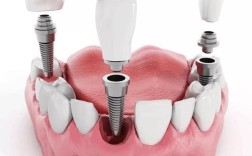

种植牙是通过外科手术将纯钛种植体植入牙槽骨内,待其与骨组织结合(骨结合)后,再在上方安装基台和牙冠,模拟天然牙的结构与功能,其优势包括不损伤邻牙、稳定性强、使用寿命长等,已成为国际公认的牙齿缺失修复首选,种植牙的成功依赖充足的牙槽骨支持——骨的高度、宽度及密度需满足种植体植入的要求,若缺牙时间过长、牙周病或外伤导致牙槽骨萎缩,骨量不足时,种植体可能无法获得初期稳定性,或长期受力后出现松动、失败,此时骨粉植入便成为关键步骤。